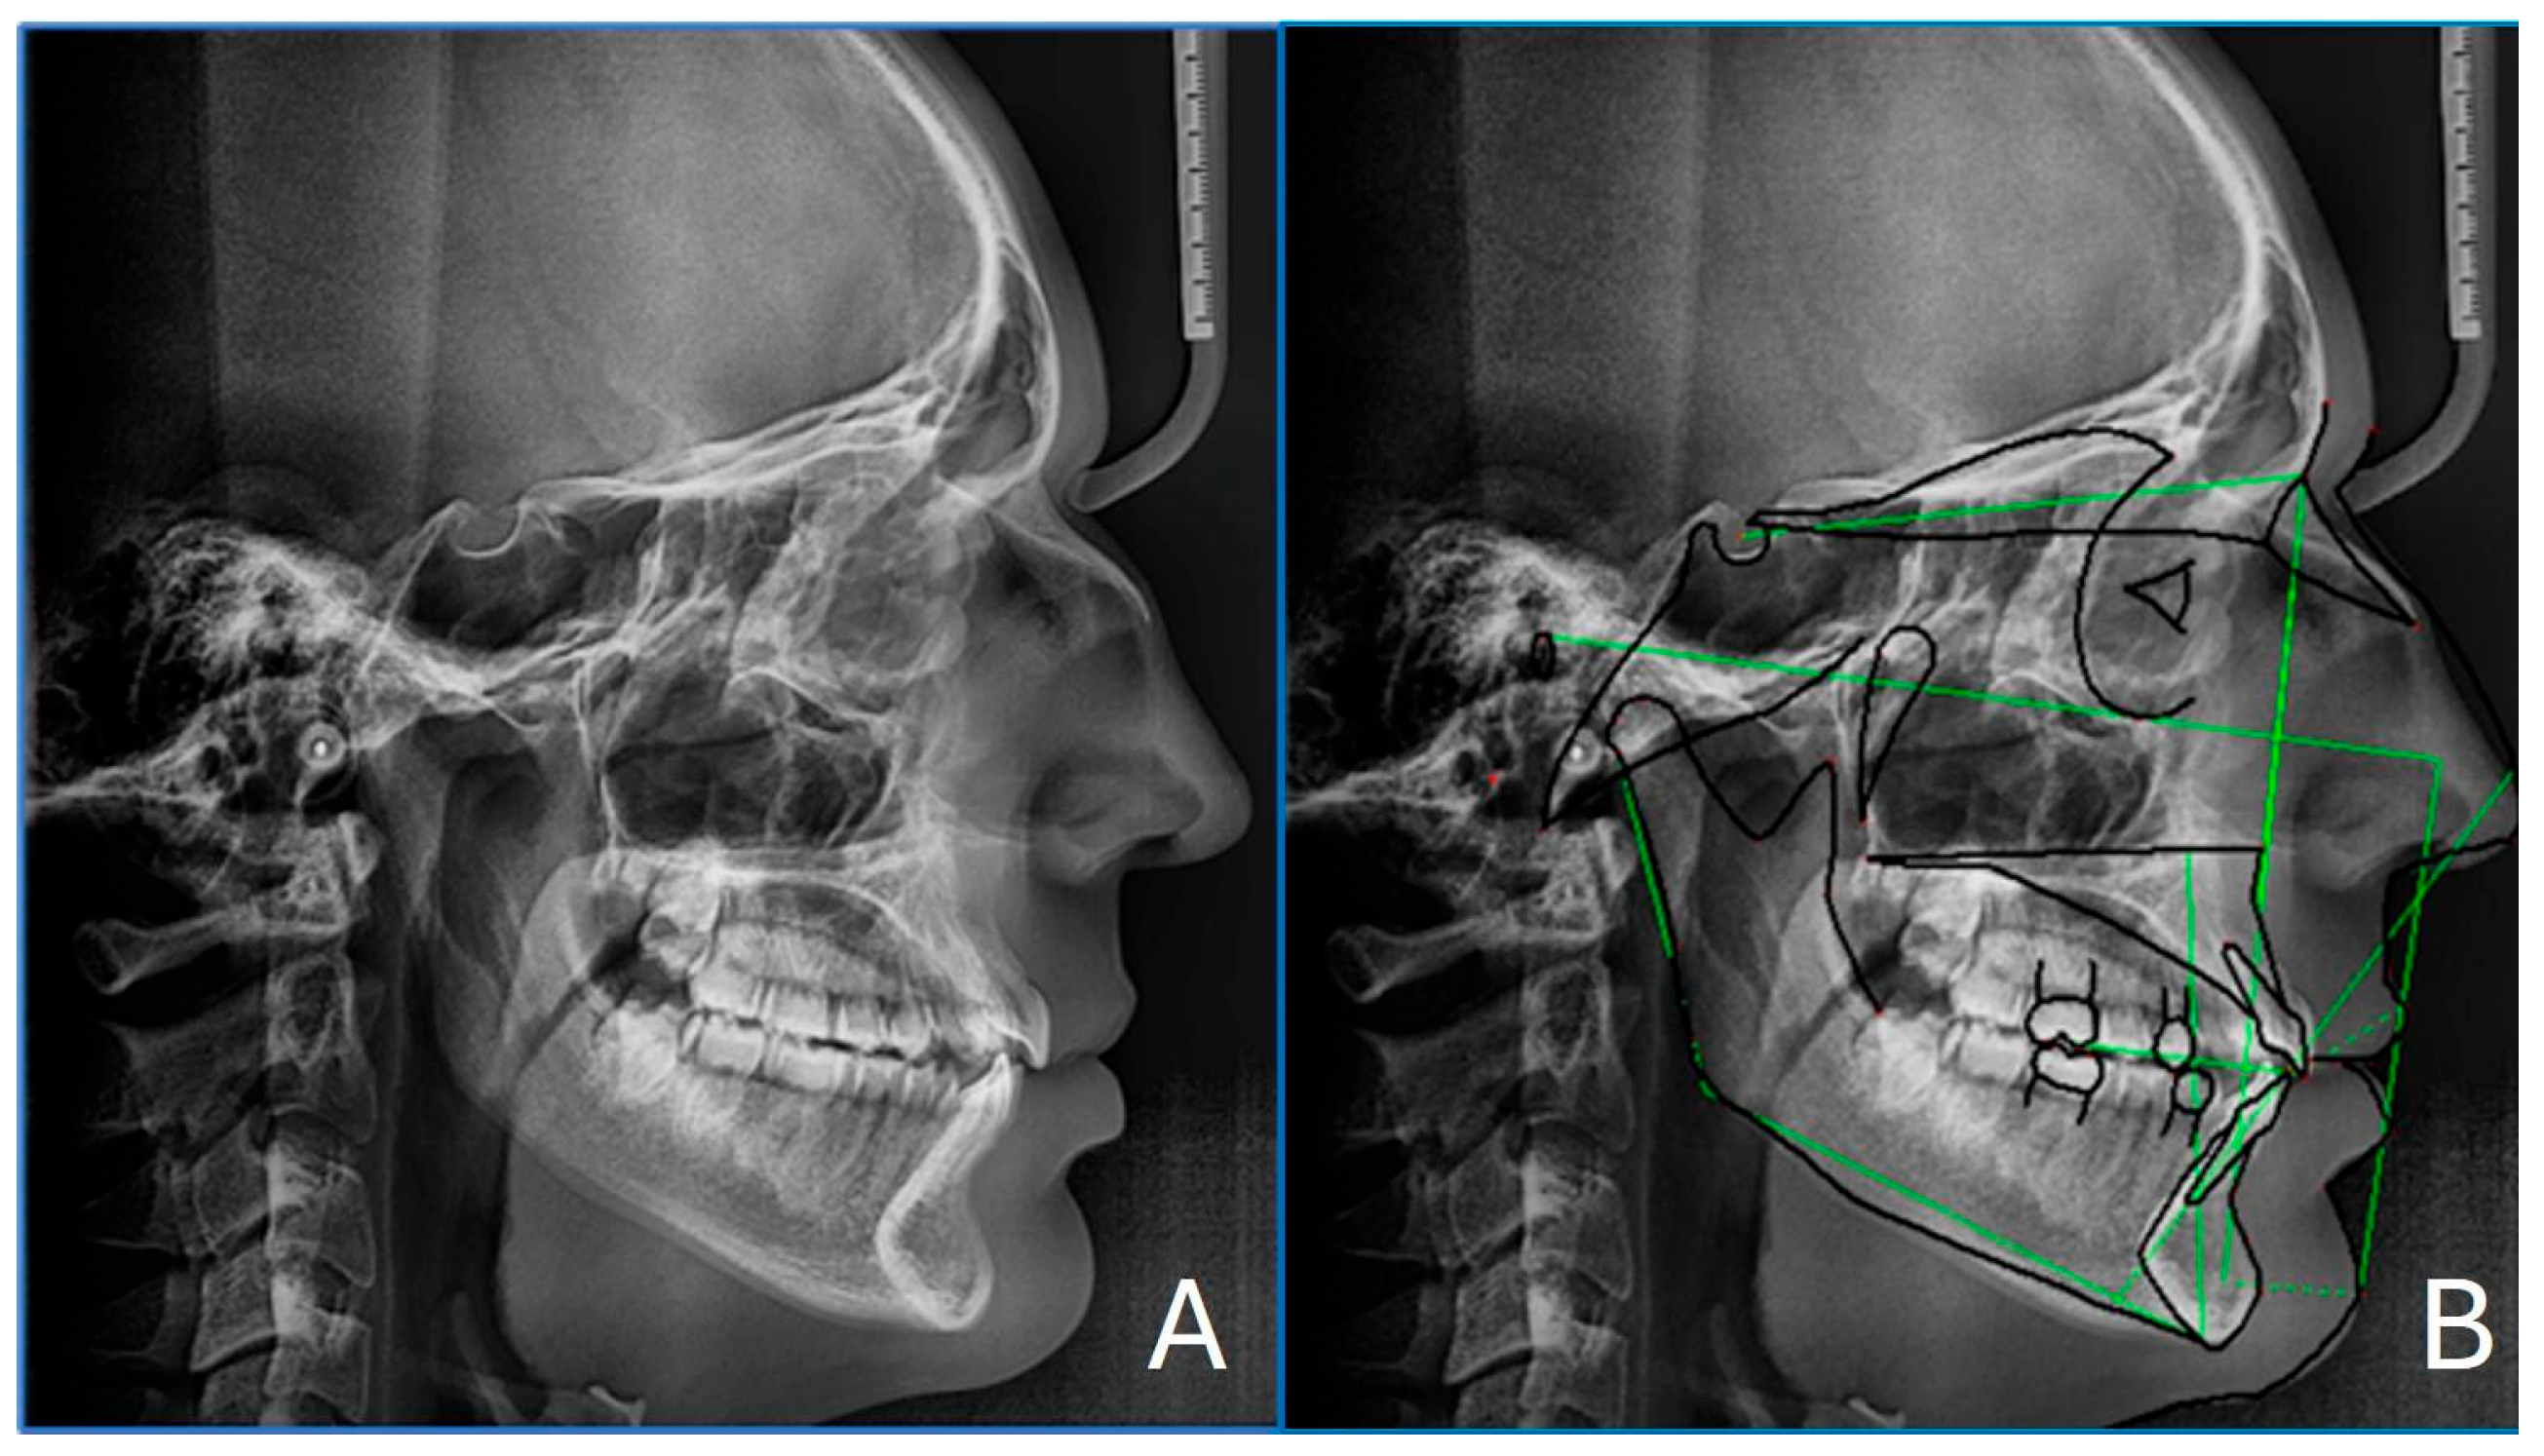

2.4. Cephalometry

| Parameter | Patient Value | Normal Range | Interpretation |

|---|---|---|---|

| SNA (°) | 80.0 | 82 ± 2 | Normal maxillary position |

| SNB (°) | 80.2 | 80 ± 2 | Normal mandibular position |

| ANB (°) | −0.1 | 2 ± 2 | Skeletal class I |

| Wits appraisal (mm) | −0.1 | 0 ± 1 | Skeletal class I |

| FMA (°) | 20.1 | 25 ± 4 | Hypodivergent growth pattern |

| Interincisal angle (°) | 120.4 | 128 ± 5 | Proclined incisors |

| A to N–Perp (mm) | −3.5 | 1 ± 2 | Retruded maxilla (McNamara) |

| Pog to N–Perp (mm) | −3.1 | 0 ± 2 | Retruded chin point (McNamara) |

| FH to AB (°) | 86.5 | 81 ± 3 | Skeletal Class III (McNamara) |